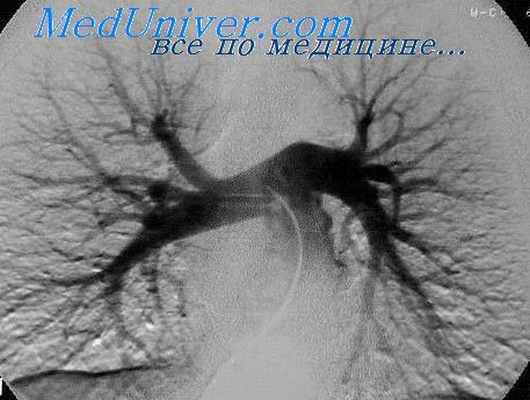

Ангиопульмонография

Ангиопульмонография – метод рентгенологической диагностики состояния лёгочного кровообращения путём введения рентгеноконтрастных веществ в артерии лёгких. Выделяют общую и селективную ангиопульмонографию. При общей ангиопульмонографии контрастное вещество вводят в ствол лёгочной артерии, при этом заполняются все сосуды малого круга кровообращения. При селективной контраст вводится лишь в одну из ветвей лёгочной артерии и оценивается состояние кровотока только одного лёгкого или его доли.

Во время выполнения ангиопульмонографии пациент лежит на операционном столе. Перед началом исследования пациенту делают местную анестезию. После пункции бедренной вены (прокола её стенки), в неё вводят проводник, по которому затем проходит катетер. Катетер проводят через правые отделы сердца, сначала в предсердие, из него в желудочек, откуда катетер попадает в ствол лёгочной артерии. Если выполняется общая ангиопульмонография, то в этом месте начинают введение контрастного вещества. Для селективной ангиопульмонографии необходимо провести катетер в одну из ветвей легочной артерии - правую или левую. Для диагностики тромбоэмболии легочной артерии или тромба в нижней полой вене применяют доступ через подключичную вену или внутреннюю яремную вену.

Во время введения контрастного вещества в лёгочную артерию у пациента может появится чувство прилива крови к лицу, солёный привкус во рту. Одновременно с введением контраста выполняется скоростная рентгеновская съёмка в двух проекциях. В результате получается серия снимков, которые можно хранить в памяти компьютера и просматривать повторно.

Интерпретация результатов ангиопульмонографии

- При оценке результатов исследования обнаруживают патологические изгибы сосудов лёгких, участки их сужения, расширения, наличие дополнительных ветвей.

- При тромбоэмболии легочной артерии на снимке точно виден тромб, можно определить его размеры и локализацию.

- По характеру сосудистого рисунка можно судить о наличии опухоли в лёгком.

Таким образом, ангиопульмонография является золотым стандартом в диагностике тромбоэмболии легочной артерии, так как не только подтверждает наличие либо отсутствие тромба, но и определяет локализацию и размеры.